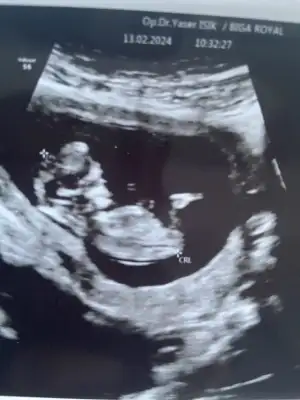

Benim kine de bakabilir misiniz 13+0Sizinki de erkek gibi geldi bana Nub ve kafasına göre

Kız gibi duruyor sizinBenim kine de bakabilir misiniz 13+0

%70 kız gibi ama bir kesinlik yok maalesef cinsiyet tahminlerinde